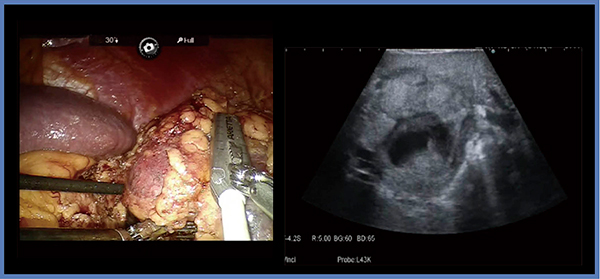

症例2は,47歳,男性,両側腎細胞がんである(図3)。本症例では左腎の4.7cmの腫瘍が腎門部にほぼ埋没しているが,このようなhilar tumorの切除にも,術中エコーが有用である。切除に当たっては,まず腎切痕よりアプローチして腎動静脈,腎盂から腫瘍をしっかりと剥離し,腫瘍の可動性が得られた時点で,エコー画像を基に切除ラインを確認し,腎実質を切除して腫瘍を切離する。その際,部位によって鈍的剥離と鋭的な切除を使い分けることで血管や尿路の不必要な損傷を防ぎ,安全に切除可能である。また,実質縫合の際,inner sutureを行うことで腎孟の縫い込みや腎血管の損傷が起きる可能性があるため,当院では基本的に一層のみで行っている。本症例は,両腎を一期的に手術したため,腎機能(s-Cre)が術前の1.17mg/dLに対し,術後1週目には2.19mg/dLと低下したが,術後4週目には1.36mg/dLにまで回復した。

図3 症例2:両側腎細胞がん(47歳,男性)